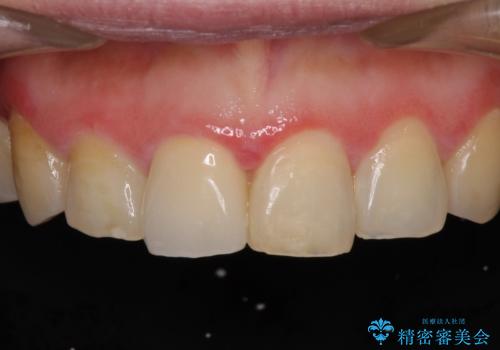

昔ぶつけた前歯 つめもの変色

- 昔ぶつけて欠けた前歯をきれいにしたい、とご来院された患者様です。

プラスチックの詰め物が長年の劣化により変色していました。

オールセラミッククラウンの治療を行いました。

以前当院でラミネート治療された患者様のご紹介で、ご来院された患者様です。

前歯2本のラミネート治療をご希望でしたが、前歯の見た目が悪いのは右上前歯1本が原因であり、左上前歯は虫歯などがなく、削るのはもったいないということをご説明しました。

また、右上の前歯は裏側までヒビが入っていることや、1層構造のラミネートよりも2層構造のオールセラミッククラウンの方が色の再現性も高いことから、右上前歯1本のクラウン治療をおすすめしました。

患者様には大変満足して頂きました。